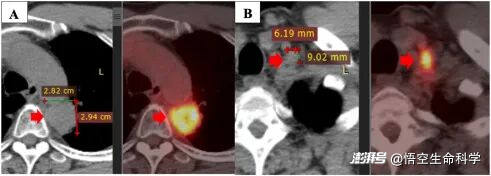

▲一線治療一年后病情進(jìn)展:原發(fā)腫瘤(A)、左鎖骨上淋巴結(jié)(B)。

▲原發(fā)腫瘤在聯(lián)合治療前后。